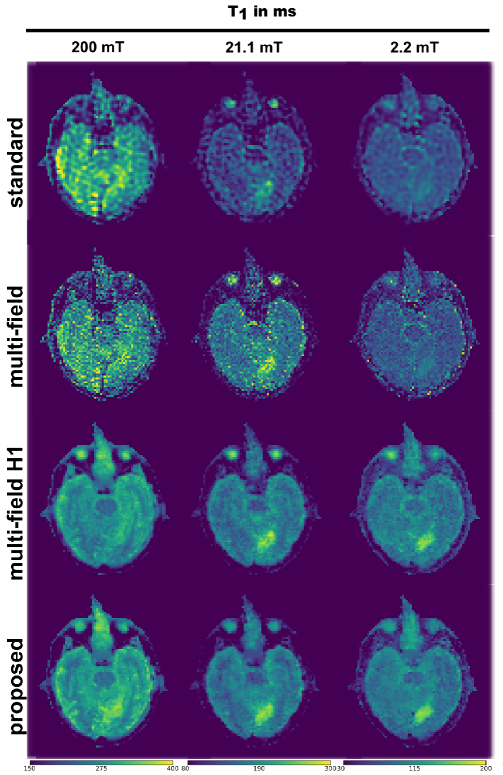

The improvements in T1subscript𝑇1T_{1} estimations held true when processing real FFC imaging data from stroke patients. The T1subscript𝑇1T_{1} maps of unfiltered FFC images obtained using standard fitting-based processing methods could not resolve anatomical features inside the brain region, as seen in Figures 6 and 7. Spatial regularization in combination with multi-field fitting could greatly improve image contrast. The proposed method offers clear distinguishable structures in T1subscript𝑇1T_{1} maps at 200 mT and is even able to recover some structural details in lower fields. It also assessed sharp features around the lesion area appearing at 37 mT and below in both patients. Fitting took approximately 65 and 150 seconds with the standard method for patient I and II, respectively, whereas the proposed method took 100 and 240 seconds for each patient, respectively.

The quality of the T1subscript𝑇1T_{1} maps obtained allowed estimating the T1subscript𝑇1T_{1} dispersion curves for different ROIs, as shown on Figure 8 for subcutaneous fat selected under the scalp, the area of the lesion observed at the lowest field strength, and white and grey matter as seen at the highest field strength (the ROIs are shown in Supporting Information Figure 1). The dispersion profiles of fatty tissues show large standard deviations, which may be attributed to the presence of various types of tissues within these ROIs, due to the relatively low resolution of the image. Otherwise, the T1subscript𝑇1T_{1} dispersion profiles of white matter, grey matter, and the areas of the lesions are similar between the two patients. This is encouraging given that the two lesion have a similar diagnosis of ischemic stroke.

The advantages of the improved fitting approach become immanent in the in vivo applications (Figures 6 and 7). The standard approaches based on pixel-wise fitting fail to reconstruct image details in both patients. In current practice, k-space windowing filters are applied to recover usable information but this dramatically reduces image resolution by filtering out the high-frequency components of the image, which are responsible for the sharp features. In contrast, the joint regularization approach can recover clearly distinguishable grey and white matter regions at 200 mT on the two patient datasets, previously hidden in noise. The values obtained for the different regions of interest agree well between the patients, given the estimation of the error provided by the variation of the T1subscript𝑇1T_{1} values within each ROI (Figure 8). The T1subscript𝑇1T_{1} values were systematically higher in patient I than in patient II, which may be attributed to patient variability and different RF receive coil sensitivity relative to the used ROIs. In addition, lesion localization agrees well with conventional MRI and CT based imaging, shown in Supporting Information Figure 1.

Figure 6: In vivo multi-field T1subscript𝑇1T_{1} maps of a transverse slice of the brain of stroke patient I. From top to bottom, T1subscript𝑇1T_{1} maps were obtained at three different evolution fields B0E={200,21.1,2.2}mTsuperscriptsubscript𝐵0𝐸20021.12.2𝑚𝑇B_{0}^{E}=\{200,~{}21.1,~{}2.2\}~{}mT by pixel-wise fitting of the signal model for each B0Esuperscriptsubscript𝐵0𝐸B_{0}^{E} separately, combined field pixel-wise fitting, multi-field model-based reconstruction with H1 regularization and by the proposed multi-field model-based reconstruction approach utilizing the joint information of all three evolution fields (bottom row).

Figure 7: In vivo multi-field T1subscript𝑇1T_{1} maps of a transverse slice of the brain of stroke patient II. T1subscript𝑇1T_{1} maps were obtained at four different evolution fields B0E={200,37,6.9,1.3}superscriptsubscript𝐵0𝐸200376.91.3B_{0}^{E}=\{200,~{}37,~{}6.9,~{}1.3\} mT. The different reconstruction methods are given in each row. From top to bottom the methods are pixel-wise fitting of the signal model for each B0Esuperscriptsubscript𝐵0𝐸B_{0}^{E} separately, combined field pixel-wise fitting, multi-field model-based reconstruction with H1 regularization and by the proposed multi-field model-based reconstruction approach utilizing the joint information of all three evolution fields.